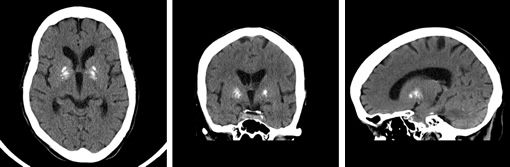

画像例(頭部)

- 120kv 390mAs/scan time 20sec